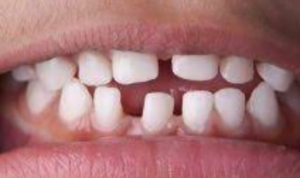

Dental development involves the replacement of the baby teeth (from...